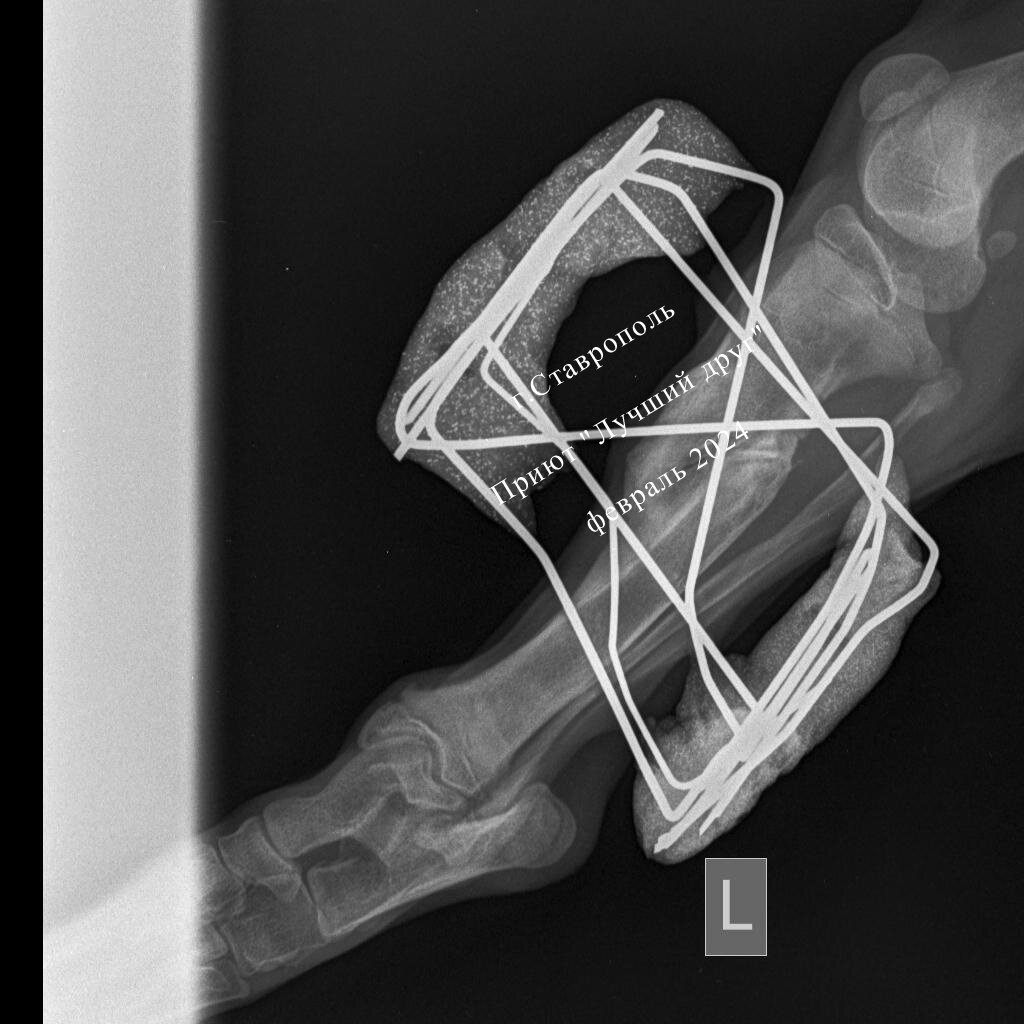

Переломы и травмы лечатся долго, операции, потом контрольные рентгены, консультации каждые 2-3 недели. Собаке надоедает всё это, что уж говорить об подписчиках канала. Посты почти под копирку, ну срастается и срастается кость, никто не вникает даже в текст и в итоге пролистывают, не читая.

А давайте немного отойдем от темы финансов и я расскажу какой Адидас замечательный щенок! В красивой шоколадной шубке, ушки торчком, отважно учится ходить на поводке и не боятся окружающий мир. Ему уже сняли спицы, он полностью поправился, впереди поиск дома и счастливая долгая жизнь.

Счет за снятие спиц 2380 руб

Долга за лечение 509 руб Реквизиты приюта: